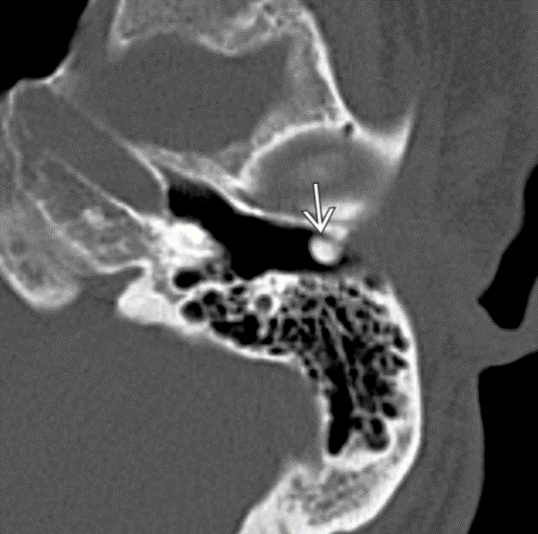

Prolapsing facial nerve (protruding intratemporal facial nerve)

Tubular soft tissue prolapsing into oval window niche from undersurface of LSC. Caused by dehiscence of bony covering of the facial nerve.

No enhancement! If enhances then it is a Schwannoma.

May project into oval indow.